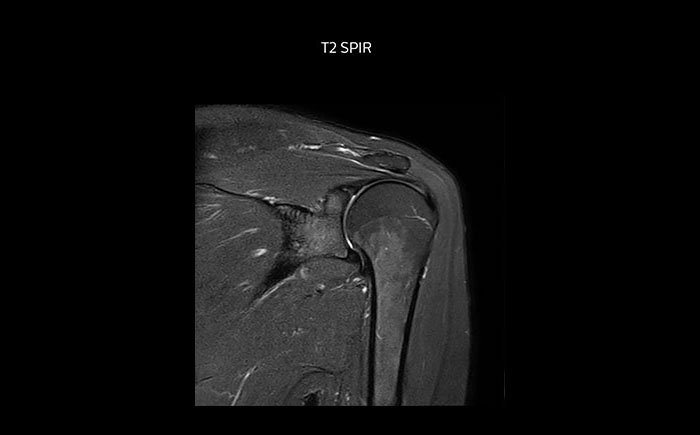

The Prodiva shoulder coil is very flexible and has large coverage, which makes good positioning easier, and that contributes to the superb image quality and high SNR that we get in our shoulder exams.

Scan time 2:55 min, FOV 160 mm, acq voxels 0.55 x 0.83 x 3.0 mm.

Scan time 4:19 min, FOV 160 mm, acq voxels 0.55 x 0.80 x 3.0 mm.

Scan time 2:50 min, FOV 160 mm, acq voxels 0.70 x 0.99 x 3.0 mm.